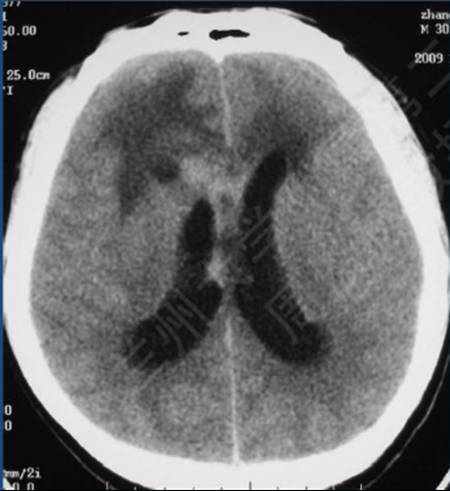

病例:男性,30岁,头痛2月

CT平扫